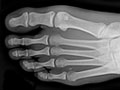

An extremity X-ray is a picture of your hand, wrist, arm, foot, ankle, knee, hip, or leg. It is done to see whether a bone has been fractured or a joint dislocated. It is also used to check for an injury or damage from conditions such as an infection, arthritis, bone growths (tumours), or other bone diseases, such as osteoporosis.

Extremity X-rays are done to:

• Find the cause of pain in an extremity.

• See if your bone is fractured or your joint is dislocated.

• See if fluid has built up in the joint or around a bone.

• See if your bones are positioned properly after treatment for a fracture or dislocation, such as after placing a cast or splint on an arm or leg. An X-ray also may be done after a doctor places a device such as a pin or an artificial joint in a bone.

• Find changes in your bones caused by conditions such as an infection, arthritis, bone growths (tumours), osteoarthritis of the hip, osteoarthritis of the knee, or other bone diseases.

• Find foreign objects such as pieces of glass or metal.

• Check to see if a child's bones are growing normally.

• See if your bones and joints are in the correct position after joint replacement surgery.